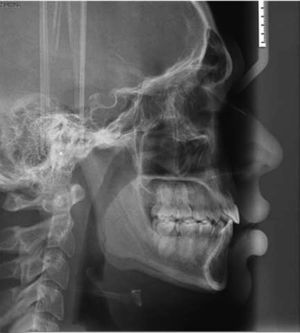

En el análisis facial se observa el tercio inferior aumentado, perfil convexo, músculos periorales hipertónicos, línea media facial coincidente con línea media dental (Figura 1).

Dentro del análisis radiográfico, se observan senos maxilares simétricos, pérdida de crestas alveolares interproximales, raíces cortas de los o.d. 31, 32, 41 y 42, ausencia de terceros molares, sólo se encuentra presente el o.d. 48. También se observa el segundo molar inferior derecho inclinado hacia mesial (Figura 3). El diagnóstico cefalométrico obtenido fue clase I esquelética, patrón braquifacial con crecimiento horizontal (C.CW 71.6%) (Figura 4).